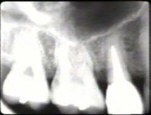

La Radiografía del lado

derecho muestra pérdida moderada del hueso periodontal con una tendencia

de bolsas infraóseas en los primeros premolares superiores.

|

La radiografía del

lado izquierdo revela pérdida moderada de hueso periodontal.

La radiografía periapical muestra al cuadrante superior derecho,

en particular

al premolar, una bolsa infraósea en mesial y distal |